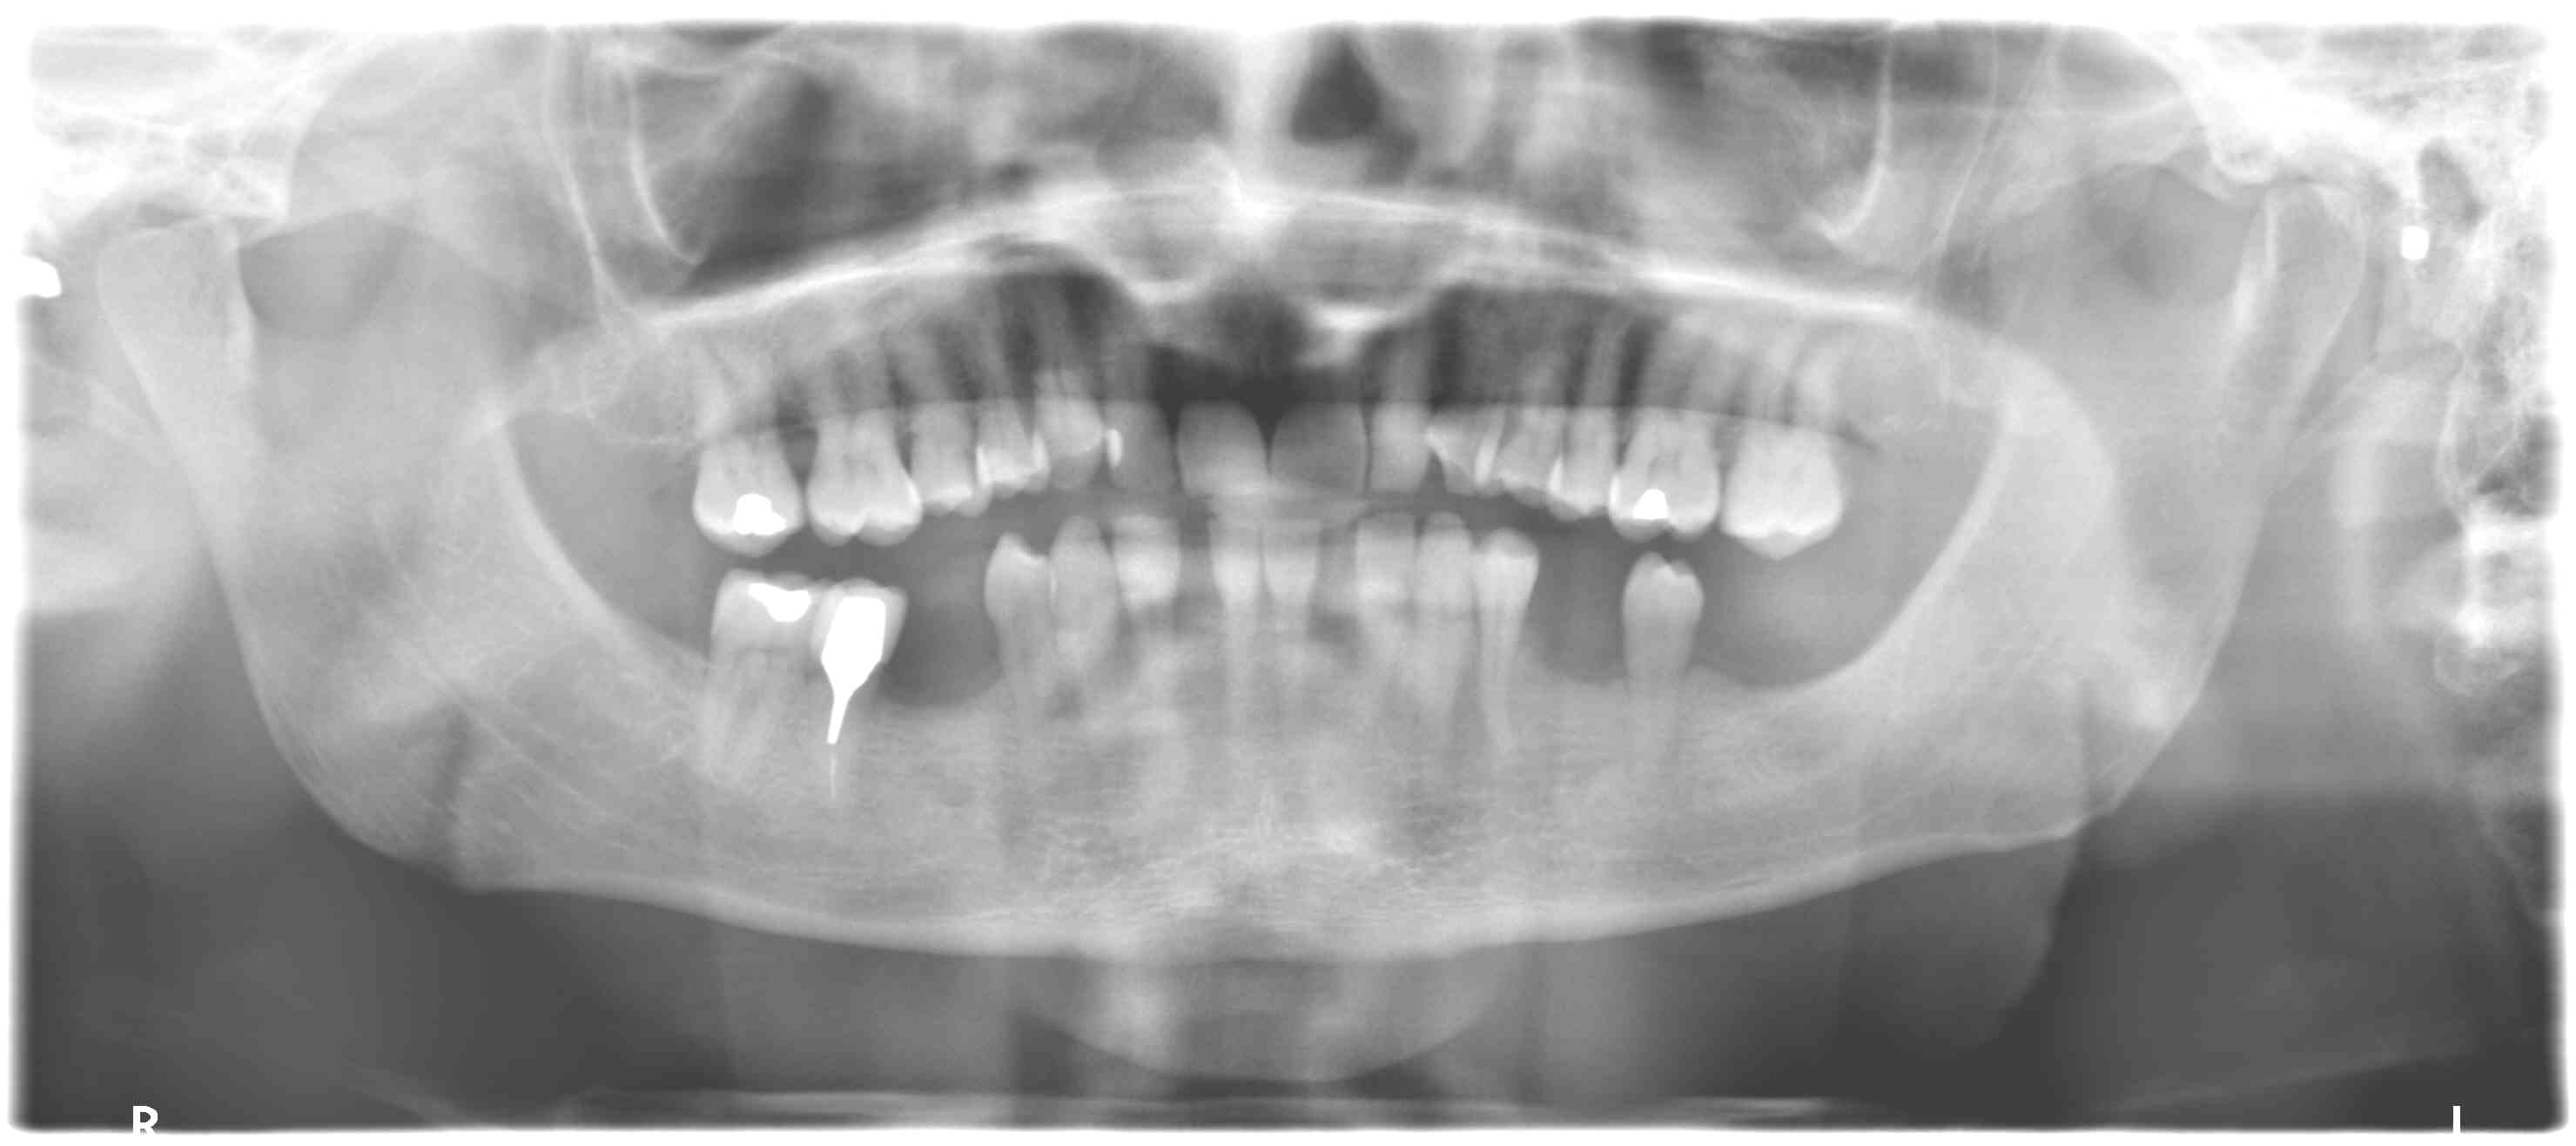

Tout frais , tout chaud...

Pour 3400 euros made in Hongrie...

Mon correspondant français malgré l'arbitrage est trop cher.

Demande de pano de la Cpam pour demande de remboursement.

Tout est jumelé, ccm et stellite, avec un patient ravi...aujourd'hui.

J'ai un doute pour la racine de 35..